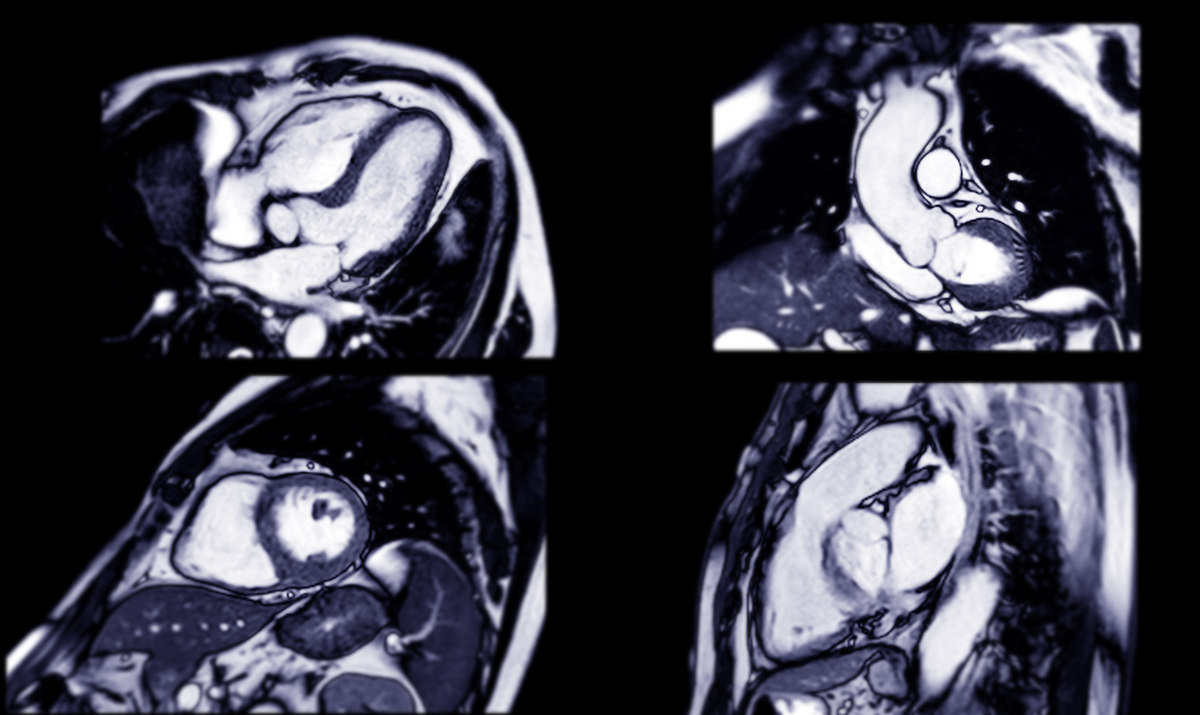

心脏核磁共振成像(Cardiac Magnetic Resonance Imaging,CMR)是一种非侵入性的心脏影像学检查方法,通过使用磁共振成像技术,可以对心脏的结构、功能、血流动力学等多个方面进行全面评估。

CMR可以提供高分辨率的图像,能够清晰地显示心脏的各个部位和组织结构,包括心腔、心肌、心包等。通过采集多个图像序列,可以评估心脏的收缩和舒张功能、心脏壁运动、心脏重构等指标,并能够检测心脏病变、心脏肌肉缺血、心肌梗死等疾病。

与其他心脏影像学检查方法相比,CMR不需要使用放射性物质,对患者无创伤性,安全性高,适用范围广,特别是对于心脏病变的早期诊断和治疗监测具有重要意义。